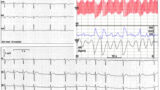

QRSは通常、正常な洞調律と同じであるためnarrow QRSとなります。心房への逆行性伝導がある場合はQRS波の終末部に逆行性P波がみられることがあります2)。

接合部異所性頻拍では多くの場合、房室解離がみられます。心房の興奮頻度を接合部頻拍が上回ることで、解離したP波が遅れていく所見が見られることもあります。